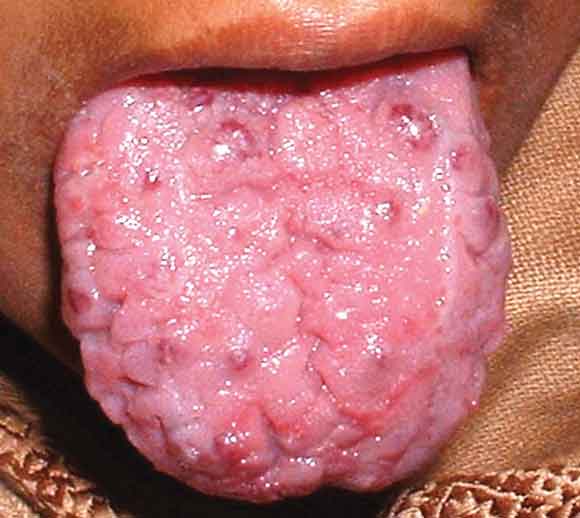

On examination, the patient had cyanosis and clubbing (Box 1), and a lumpy tongue (Box 2) suggestive of tongue telangiectasia. A chest x-ray showed left mid-zone opacity (Box 3), which was confirmed to be a pulmonary arteriovenous malformation (AVM) on spiral computed tomographic angiography (Box 4). Transcutaneous embolotherapy produced a marked improvement in her symptoms. The patient is currently asymptomatic and undergoing regular follow-up.

The patient has hereditary haemorrhagic telangiectasia (Osler–Weber–Rendu disease), an autosomal dominant disorder related to mutations on chromosomes 9 and 12. Clinical diagnosis is based on the findings of epistaxis, telangiectasia, visceral AVMs and family history. Fulfilling three of these criteria indicates a definite diagnosis; two, a possible case. In our patient, the presence of three of the four manifestations confirmed the diagnosis.